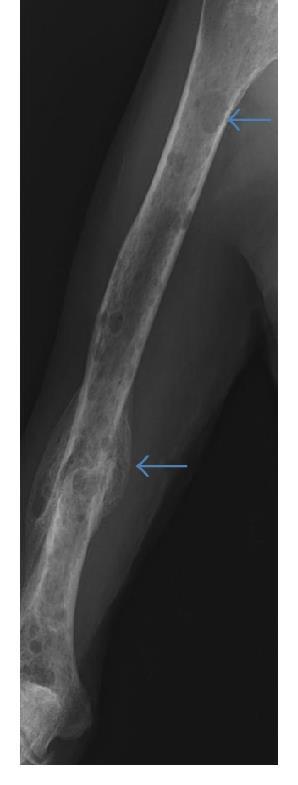

Conventional X-rays reveal punched-out lytic lesions, osteoporosis, or fractures in 75% of patients.

FDG PET/CT appears to be more sensitive (85%) than skeletal survey for the detection of small lytic bone lesions.

Multiple Myeloma •

Kyle RA et al. Mayo Clin Proc Jan;78(1): 2003. Nanni Cet al. European Journal of Nuclear Medicine and Molecular Imaging Vol.33:2006 Dimopoulos MA, et al. Leukemia. 2009 • Diagnosis is confirmed with bone marrow demonstrating greater than 10% involvement by malignant plasma cells with either CRAB or SLiM Malignant Plasma cells seen on biopsy AND ≥1 “CRAB” feature OR have >1 SLiM ‘high risk” features: C: Calcium elevation(>11mg/dL) R: Renal- low kidneyfunction; (serumcreatinine >2mg/dL) A: Anemia –low redblood count (Hb <10 g/dL) B: Bone disease (≥1 lytic lesionson skeletalradiography, CT, or PET-CT) S: >60%PlasmaCells onBoneMarrow biopsy Li: Serumlightchainratio >100 M:>1 lytic lesionsonMRI (or PET/CT scan)